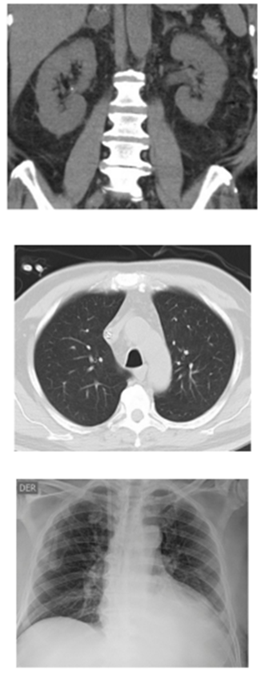

Al examen físico se describe la presencia de edemas en miembros inferiores sin oliguria. En estudios de laboratorio de ingreso se evidencia un uroanálisis con hematuria, proteinuria y sedimento urinario activo, función renal alterada. Dados los hallazgos de sedimento activo, se deciden solicitar estudios adicionales en los cuales se documentó la presencia de proteinuria significativa en rango nefrótico 4 gr/dl, resultado no explicable únicamente por nefropatía diabética. Se realizó una ecografía renal y un tracto urinario que demostró que los riñones derecho e izquierdo no tenían obstrucciones y sí había aumento de la reflectividad cortical, de 11,8 y 12 cm respectivamente.

Durante su hospitalización, el paciente presenta un deterioro persistente de la función renal, progresando a lesión renal aguda KDIGO 3 con criterios de urgencia dialítica, por lo cual se comienza terapia de remplazo renal tipo hemodiálisis intermitente. Ante la persistencia de las manifestaciones clínicas y los paraclínicos alterados, entre ellos se resalta el sedimento urinario activo y el perfil de autoinmunidad comprometido, se decide realizar una biopsia renal y comenzar manejo con inmunosupresión por sospecha de glomerulonefritis rápidamente progresiva secundaria a patología autoinmune tipo vasculitis primaria.